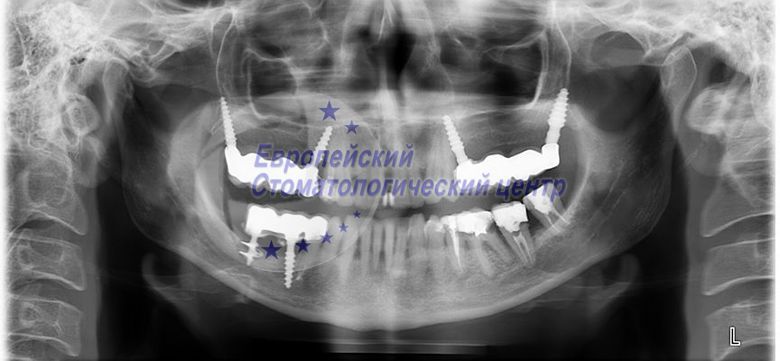

опг через 5 лет после операции